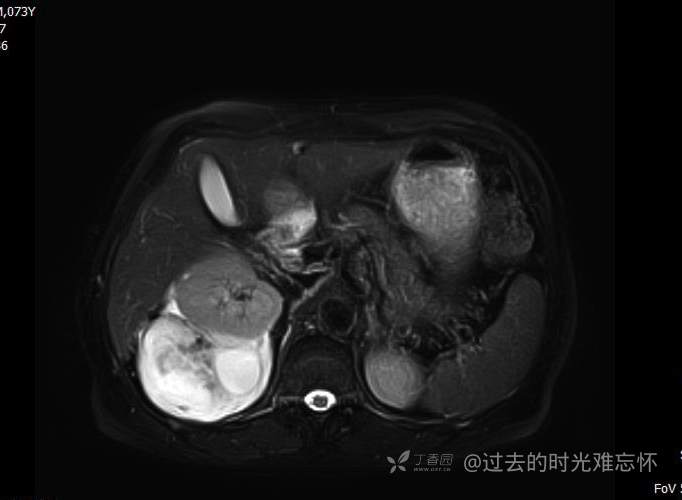

患者性别:男

患者年龄:73岁

主诉:咳嗽1月余。曾有血尿一次。后背部酸痛不适1-2年左右,无明显消瘦。

辅助检查:CT MRI

临床诊断:占位

治疗经过:手术

增强

黏液样脂肪肉瘤 (12)